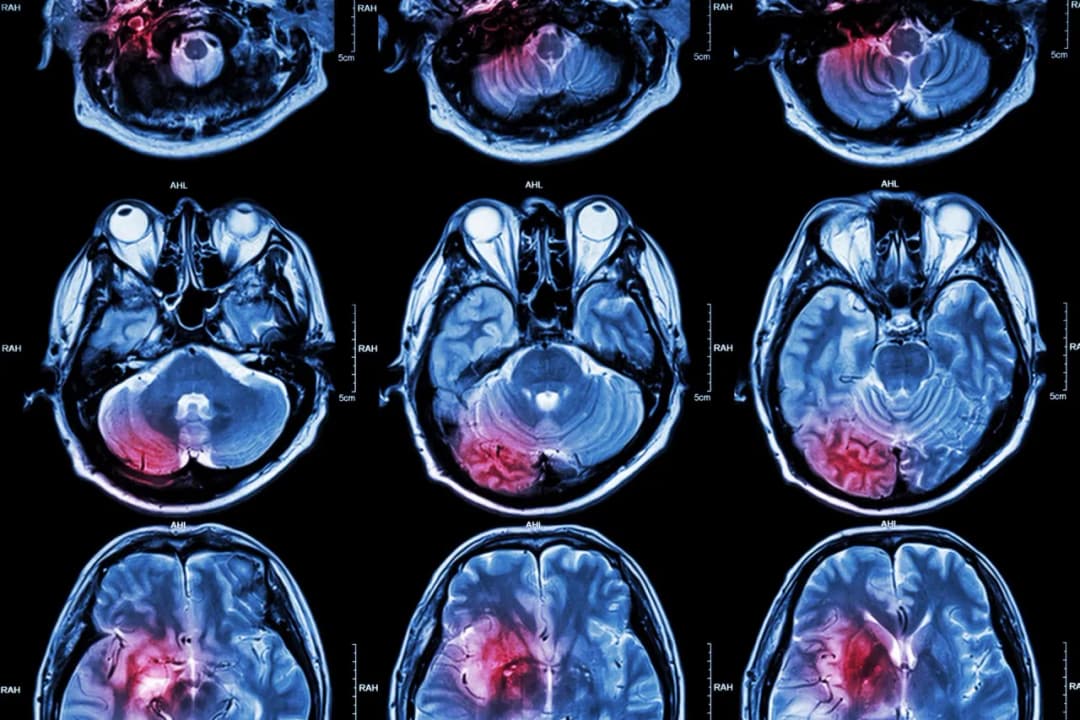

Tag udar móżdżku pierwsza pomoc